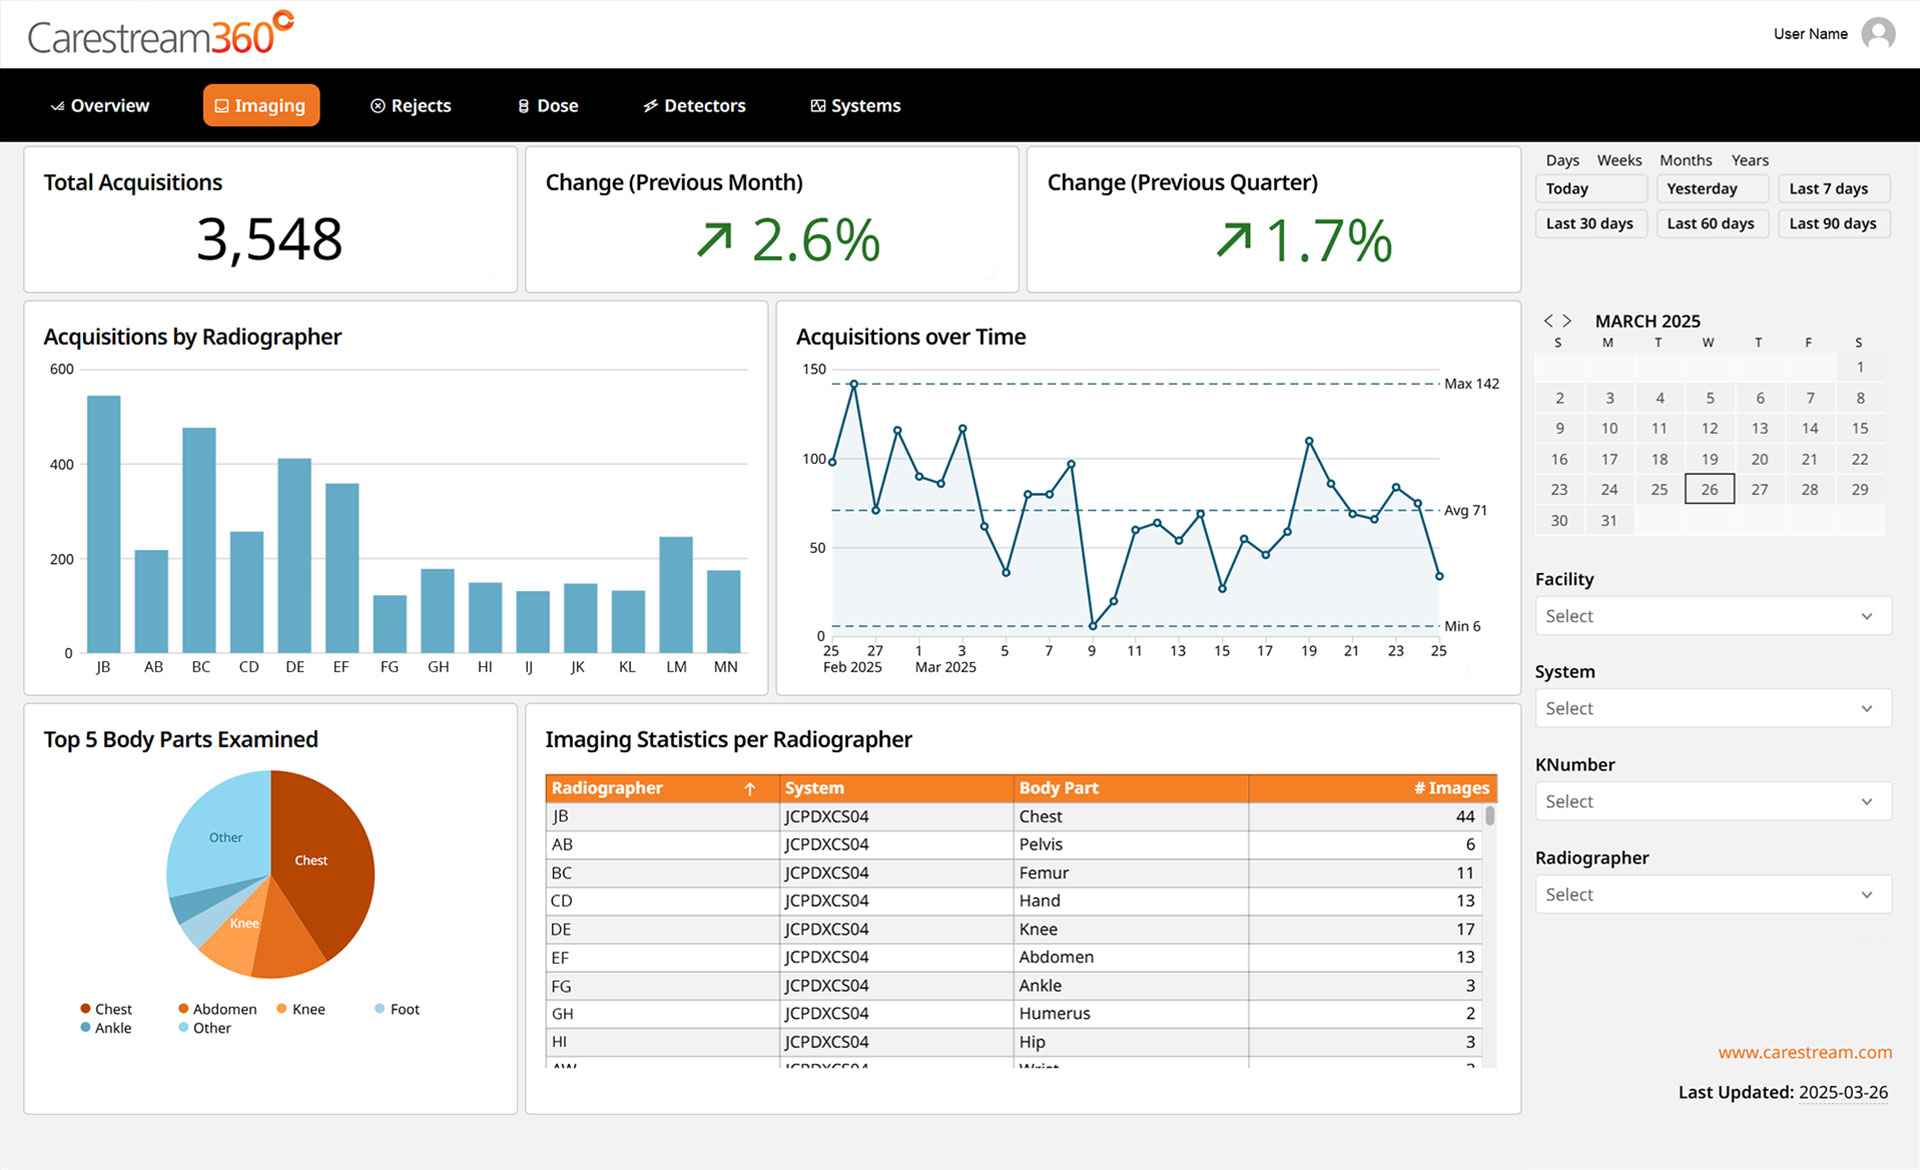

Carestream 360º is an advanced analytics dashboard designed to help radiology departments track key performance metrics, analyze imaging trends, and optimize operational efficiency. It automatically collects critical data from all connected Carestream DR systems and consolidates it into a single, intuitive dashboard, providing a comprehensive view to drive smarter decision-making.

Carestream 360º is designed with interactive tools that allow you to filter, explore, and export data effortlessly, empowering you to gain insights faster, interact intuitively, and make informed, data-driven decisions.

- Filter with Ease – Quickly refine data using intuitive, pre-set filters that allow you to focus on the metrics that matter most.

- Drill-Down Analysis – Dive deeper into trends and performance metrics to support more informed decision-making.

- Exportable Cards – Easily extract key insights for sharing, reporting, or further analysis.

Carestream 360º transforms complex performance metrics into clear, actionable insights through a series of intuitive dashboard pages. Designed for efficiency, it helps you: